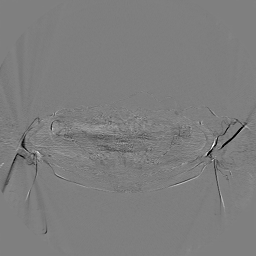

To assess the uncertainty of our method, we performed multiple reconstructions using different random seeds. As shown in Fig. 3, the ground truth and representative sampled images are presented in Fig. 3(a) and (b–d), respectively. The mean reconstruction and pixel-wise standard deviation across runs are displayed in Fig. 3(e) and (f). Only minimal differences are observed between reconstructions, indicating that I2SB produces highly consistent results. These findings confirm that, compared with classical diffusion models, I2SB substantially reduces uncertainty across repeated reconstructions.